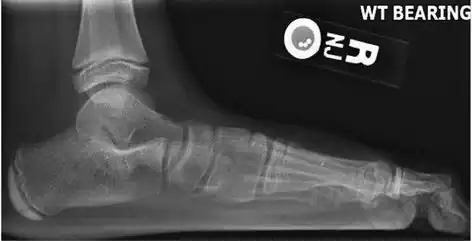

Weight-bearing lateral X-ray showing the measurement of calcaneal pitch, which is an angle of the calcaneus and the inferior aspect of the foot, with different sources giving different reference points.[13] A calcaneal pitch of less than 17° or 18° indicates flat feet.[11]

Same lateral X-ray showing the measurement of Meary's angle, which is the angle between the long axis of the talus and first metatarsal bone.[11] An angle greater than 4° convex downward is considered a flat foot, 15° - 30° moderate flat foot, and greater than 30° severe flat foot.[11]